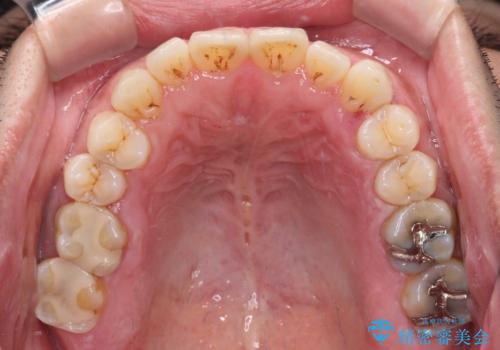

口腔内は非常にきれいで、定期的に歯科医院でのクリーニングも行っているとのことでしたが、歯肉からの出血が一向に解決しない状態でした。

奥歯の歯間部の歯肉が炎症で赤黒くなっており、歯周ポケットを検査したところ、6-8mm(正常では3mm以下)であり、外科処置が適用となる状態でした。

まずは仮歯に置き換え、歯周ポケットを除去するための外科処置(歯肉弁根尖側移動術)を行い、治癒を待ってセラミッククラウンにて補綴治療を行うこととしました。